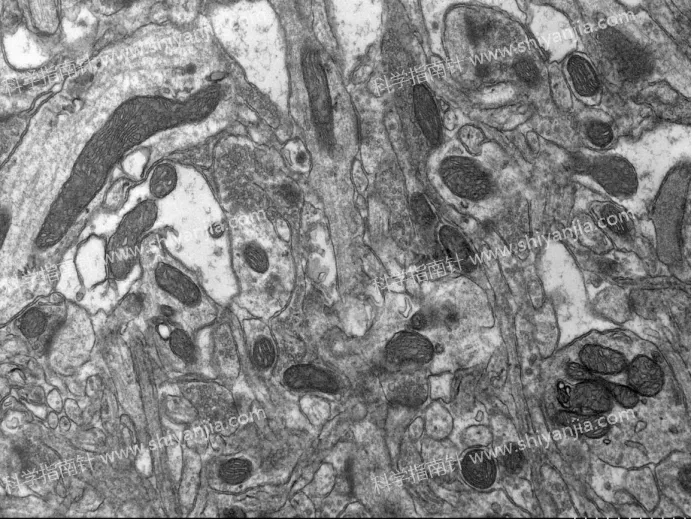

4.不同结构耐受度不同:髓鞘和突触对短时间缺血具有相对耐受性,受灌注处理和短时间取材延迟的影响较小。

2.观测突触、髓鞘结构时,可省略灌流步骤,直接开展快速取材,减少实验操作步骤。